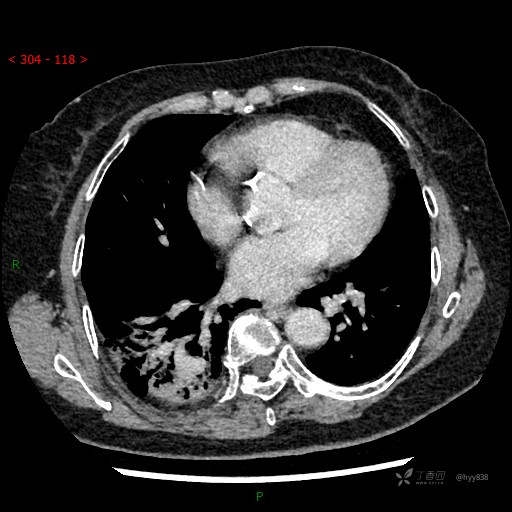

胸部CT平扫

增强动脉期